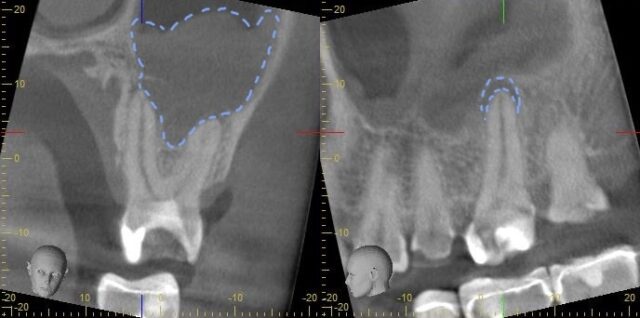

レントゲン写真、CTでも見てみましょう

黄色く囲っているところはカリエスで、青く囲っているところは根尖病変ができてしまっているところです。

上の歯は上顎洞といって鼻に繋がる空洞があるのですが、今回の歯はその上顎洞の粘膜まで肥厚してしまっています。

6ヶ月後のCTがこちらです。

根尖病変ができていたところには骨ができ、上顎洞の肥厚も大きく縮小しました。